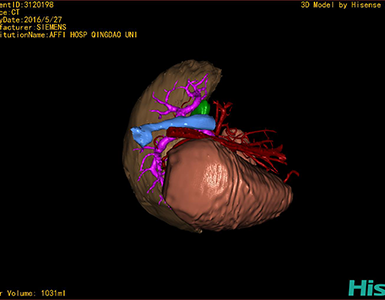

CT结果输入海信CAS系统后行3D重建及手术规划后,于2016-6-28全麻下行“劈离式肝移植(左半肝,背驮式)”手术治疗。

将0.625mm双源薄层CT资料的静脉期和动脉期Dicom格式文件导入海信CAS系统。

通过调节窗宽窗位调整CT序号,对肝实质,胆囊,下腔静脉,肝动脉、门静脉及肝静脉等进行三维重建,明确血管走行;系统自动计算肝脏体积。

模拟手术操作,肝脏体积为1052ml,通过比对11-12岁正常肝脏体积为1116.86±158.78ml,建议进行肝移植手术。

术前手术方案的规划。

术前三维重建:

重建图片